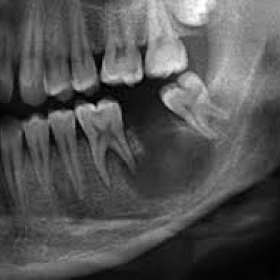

Киста может располагаться касательно по отношению к верхушке корня зуба, но может и окружать его со всех сторон . Если на снимке на контур кисты накладывается изображение корней соседних зубов, следует проследить целостность их периодонтальной щели . Если последняя нарушена, это является признаком вовлечения других зубов в структуру кисты .

Как выглядит киста зуба на рентгене . Что такое киста зуба? Киста зуба возникает, когда организм пытается справиться с инфекцией, занесенной в корневой канал зуба . Зараженные клетки отмирают, и вокруг омертвевшего участка возникает плотная оболочка — капсула . . .